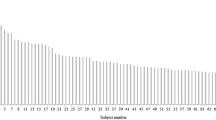

The arising direction of the initial segment of the RRA was measured in axial images, with a horizontal and a perpendicular straight line made through the center of the aorta where the RRA originated. Hour hand positions of 9–12 o’clock were projected and fused with the lined images, and the RRA arising directions were recorded as the hour hand positions (Fig. 1c, 2b).

The most common RRA arising orientation of the 44 patients were 10:00 and 10:30 (Table 1; Fig. 1c), with 17 (38.64%) and 12 (27.27%) cases, respectively, and with 3 (6.82%), 6 (13.64%) and 6 (13.64%) cases at 9 o’clock, 9:30, and 11 o’clock (Fig. 2b), respectively. There was no noticeable orientation difference between the groups and subgroups. Accessory right renal arteries were seen in 5 cases (4 Renal and 1 Non-renal), compressing the end of the LRV in 1 Renal patient.